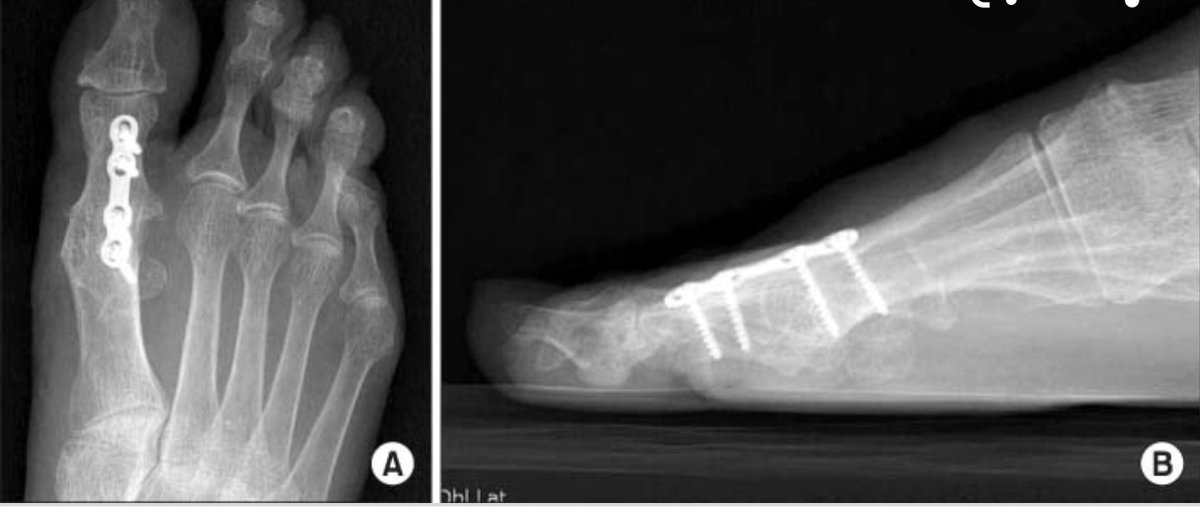

العلاج الجراحي في الحالات غير المتقدمة (التي لم تتحسن بالعلاج غير الجراحي) :

-إزالة الزوائد العظمية وتحسين حركة المفصل

-اعادة تقويم المفصل

العلاج الجراحي بالحالات المتقدمة:

١-تغيير المفصل بإضافة مادة خاصة لتغطية سطح المفصل

Hydrogel polymer

٢-تثبيت المفصل نهائيا